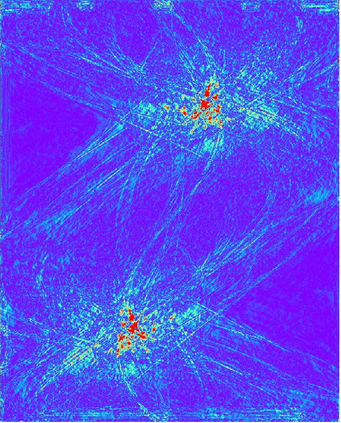

Low-Dose Computed Tomography (LDCT) technique, which reduces the radiation harm to human bodies, is now attracting increasing interest in the medical imaging field. As the image quality is degraded by low dose radiation, LDCT exams require specialized reconstruction methods or denoising algorithms. However, most of the recent effective methods overlook the inner-structure of the original projection data (sinogram) which limits their denoising ability. The inner-structure of the sinogram represents special characteristics of the data in the sinogram domain. By maintaining this structure while denoising, the noise can be obviously restrained. Therefore, we propose an LDCT denoising network namely Sinogram Inner-Structure Transformer (SIST) to reduce the noise by utilizing the inner-structure in the sinogram domain. Specifically, we study the CT imaging mechanism and statistical characteristics of sinogram to design the sinogram inner-structure loss including the global and local inner-structure for restoring high-quality CT images. Besides, we propose a sinogram transformer module to better extract sinogram features. The transformer architecture using a self-attention mechanism can exploit interrelations between projections of different view angles, which achieves an outstanding performance in sinogram denoising. Furthermore, in order to improve the performance in the image domain, we propose the image reconstruction module to complementarily denoise both in the sinogram and image domain.